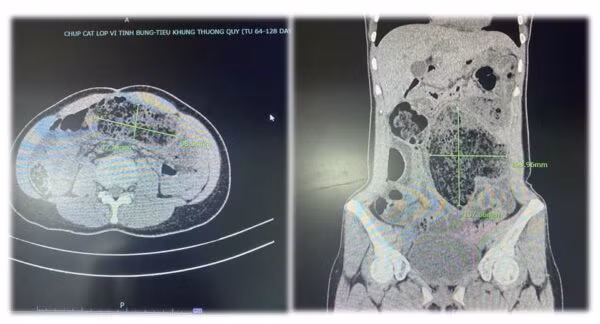

Rạng sáng 25/6/2023, người bệnh nhập viện trong tình trạng đau quặn, bụng chướng, buồn nôn. Qua thăm khám và kết quả chụp CT ổ bụng xác định chẩn đoán tắc ruột do bã thức ăn (nghĩ đến do ăn mít)

![]() |

| Hình ảnh ruột tắc trên phim chụp |